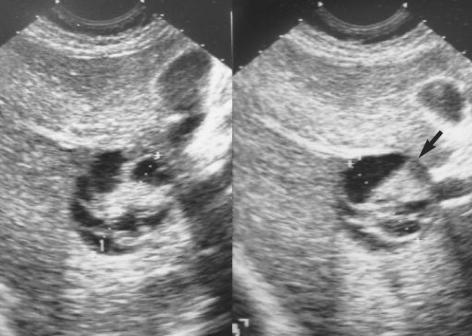

A primary benign schwannoma of the liver is extremely rare. Only nine cases have been reported in the medical literature worldwide and no case has been reported in Korea previously. A 36-yr-old woman was admitted to our hospital with vague epigastric pain. The ultrasound and computed tomography scan revealed a multi-septated cystic mass in the right lobe of the liver. The mass was resected; it was found to be a 5 x 4 x 2 cm mass filled with reddish yellow fluid. The histological examination confirmed the diagnosis of a benign schwannoma, proven by positive immunoreaction with the neurogenic marker S-100 protein and a negative response to CD34, CD117 and smooth muscle actin. This is the first report of a benign schwannoma of the liver parenchyma in a Korean patient.

原发性肝脏良性神经鞘瘤极为罕见。全球医学文献中仅报道过9例,韩国此前尚无相关病例报告。一名36岁女性因上腹部隐痛入院。超声和计算机断层扫描显示肝脏右叶有一个多分隔的囊性肿块。该肿块被切除,发现是一个5×4×2厘米的肿块,充满红黄相间的液体。组织学检查证实为良性神经鞘瘤,通过与神经源性标志物S-100蛋白的阳性免疫反应以及对CD34、CD117和平滑肌肌动蛋白的阴性反应得以证实。这是韩国患者肝脏实质良性神经鞘瘤的首例报告。